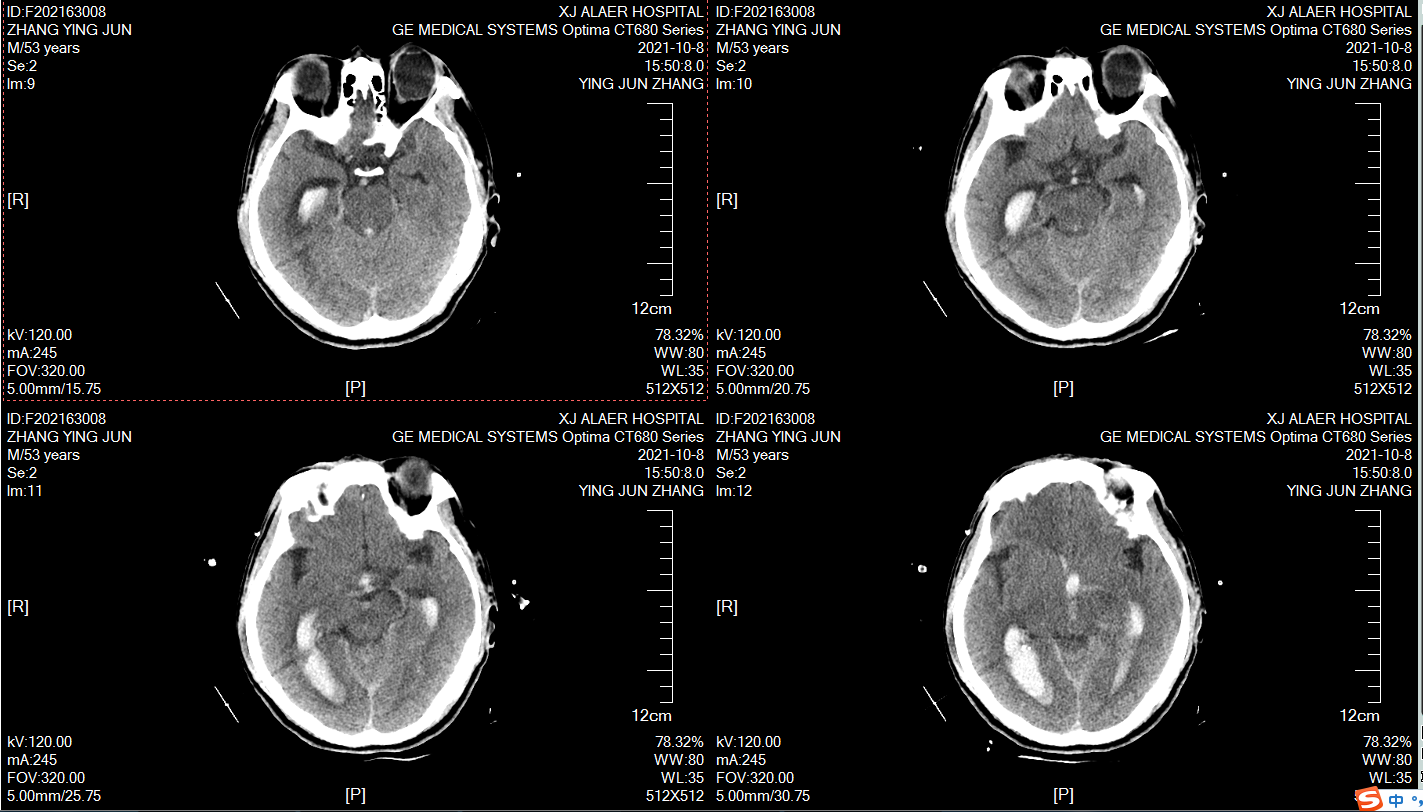

术前颅脑CT,男性,59岁,突发意识不清2小时,目前昏迷,GCS6分,右侧瞳孔4mm,左侧瞳孔2mm,脑室出血,烟雾病!